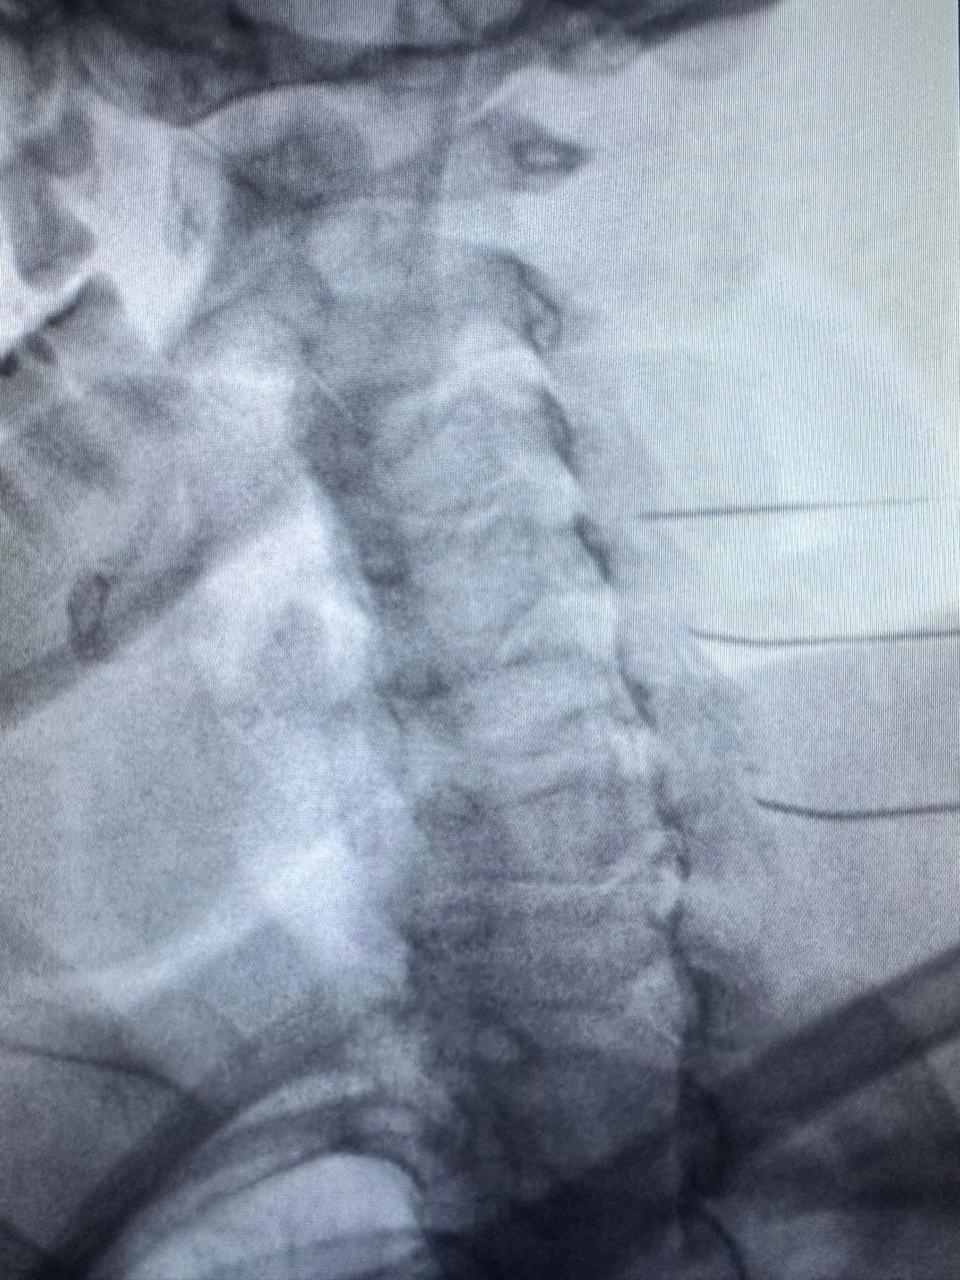

Inhibición plexo Esplacnico con Neurolisis química para tratar dolor en cancer de páncreas avanzado